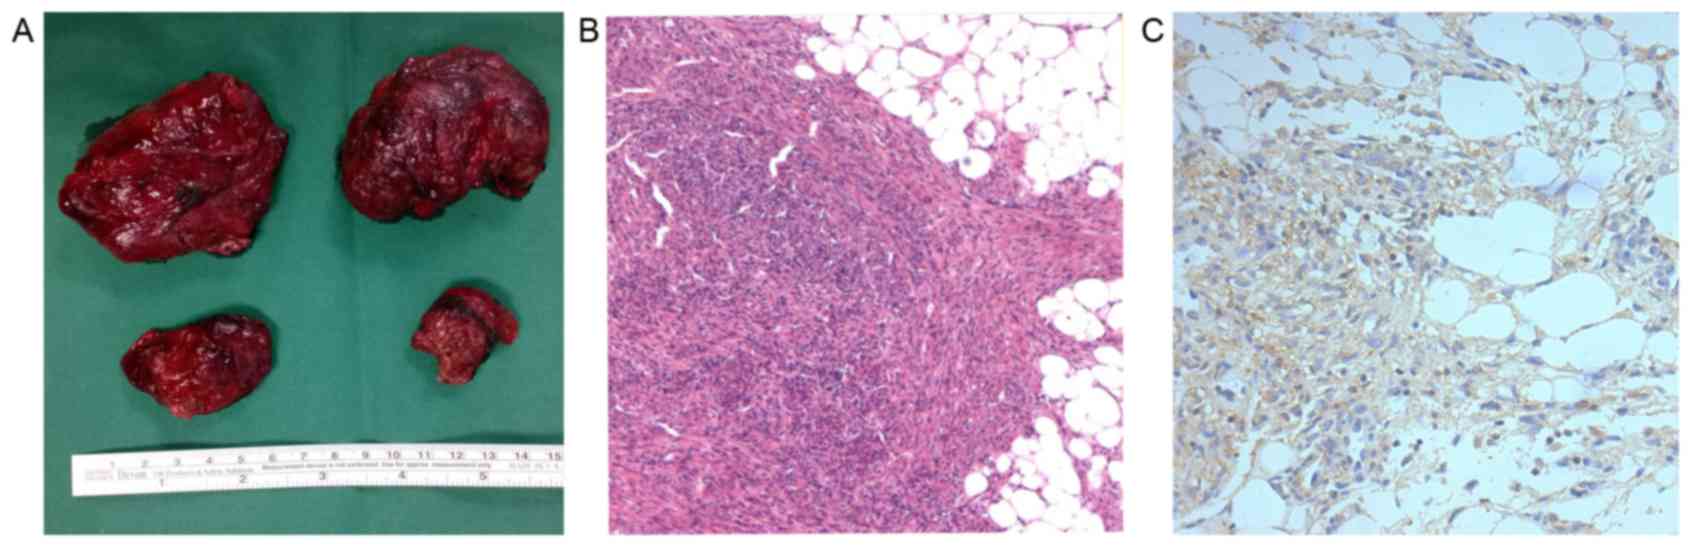

Surgical treatment and

immunohistochemical staining

Due to a high risk of bleeding, as well as the

relatively isolated and protruding nature of the RAMLs, 3 patients

underwent a partial nephrectomy by means of open surgery,

preserving the normal renal tissue as much as possible.

Pathological results showed a large number of smooth muscle cells

and fat cells, as well as certain malformed blood vessels and

aneurysms in part of the visual field. Immunohistochemistry

determined the positive expression of p-mTOR in the TSC-RAML

tissues, particularly in the cells of the vascular wall (Fig. 2).

with ineffective conservative treatment. Only 3 patients in the

present study underwent partial nephrectomy due to the high risk of

bleeding, and the pathological results showed the positive

expression of p-mTOR, indicating the excessive activation of the

mTOR signaling pathway, which also has been confirmed in TSC brain

and skin lesions (21,22). Bissler et al (23) reported preliminary results of the